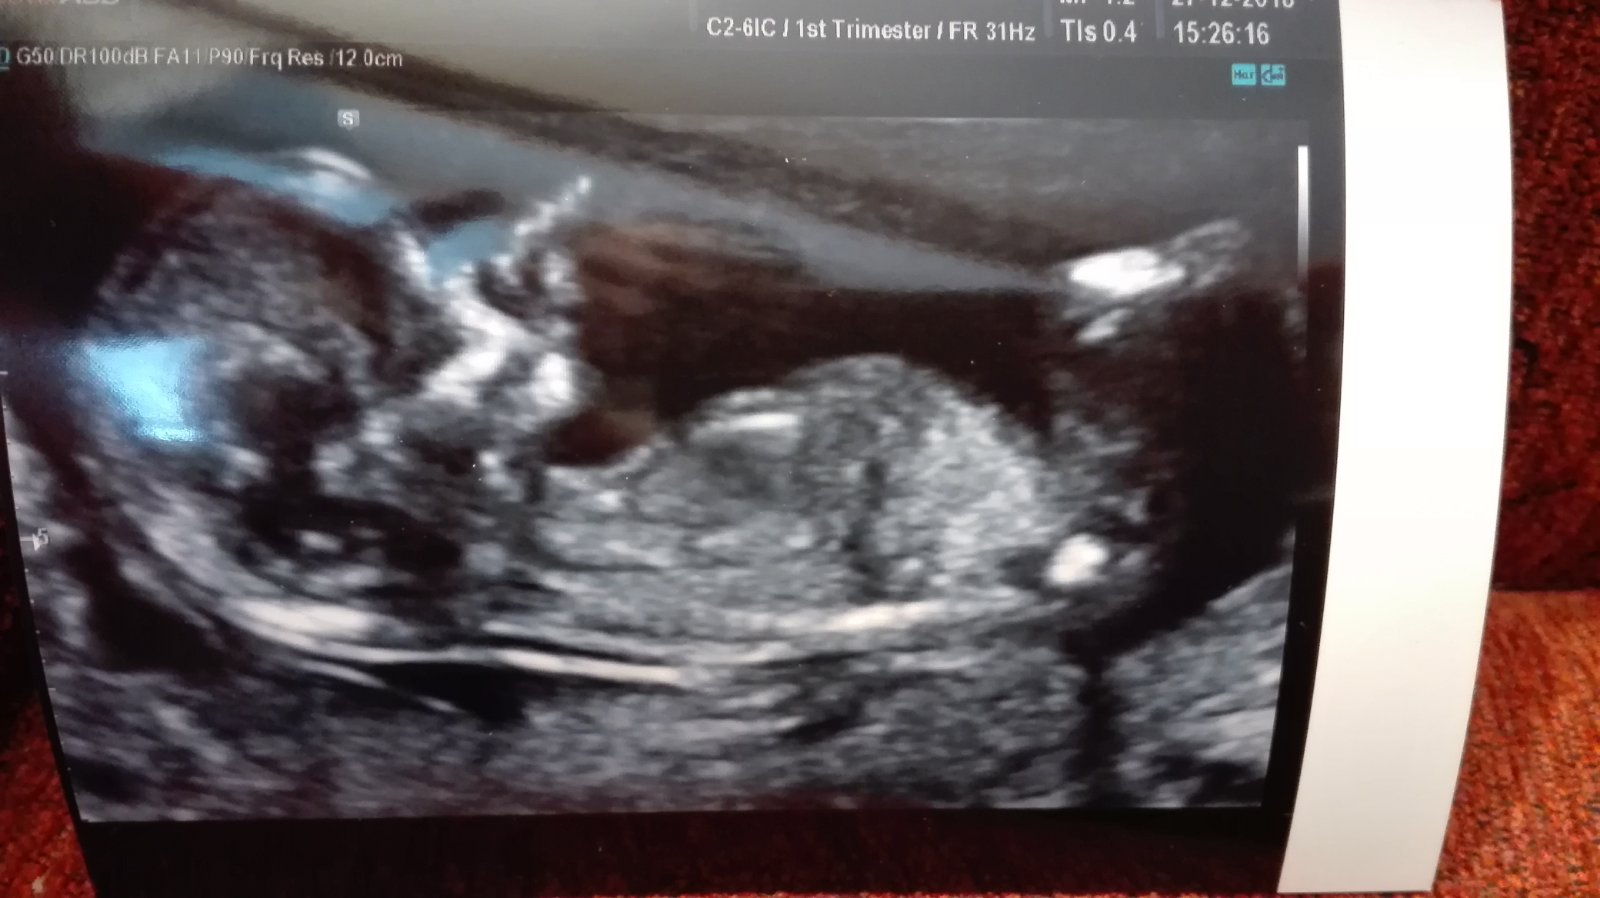

Tak u mě podle všeho další ZT ☹. Miminko menší o 12 dní (a já extra krátké cykly) jen s náznakem srdíčka. Minule to bylo úplně stejně. Doktorka mi kladla na srdce abych se snažila revizi vyhnout, další kontrola za 14 dní, to bych měla být 10+0, minule se něco začalo dít 10+6, tak snad to přijde co nejdříve...

Jinak u nás to vypadá zatím velice dobře, mimi odpovídá přesně, byli jsme na kombinovaném screeningu ve 13+0 a prý to lepší snad ani nemůže být 😍 manžel byl se mnou a fakt si to užil, byl nadšený. Doufám, že i dál půjde vše jako po másle!